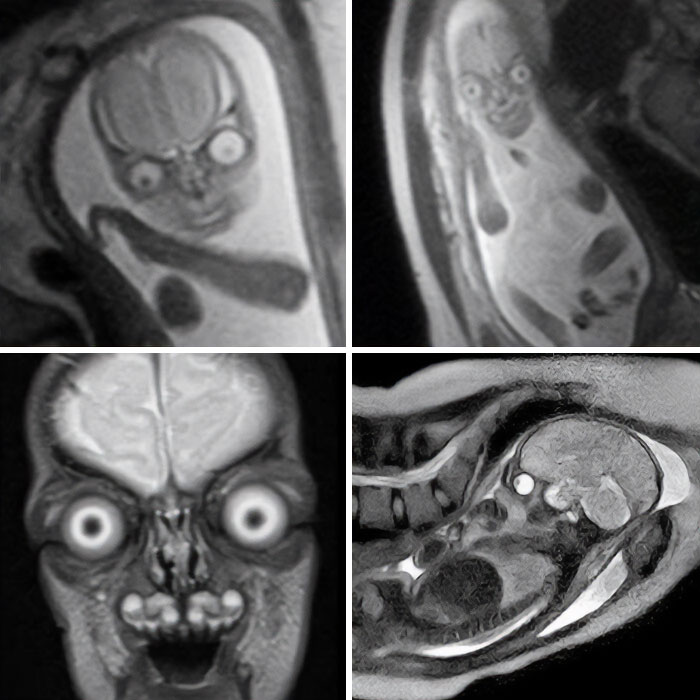

Genuine MRI Scans Of Human Babies In The Womb

Possessing menacing eyes and devilish grins, you would be forgiven for assuming these were just aliens from a Hollywood sci-fi blockbuster.

These images were circulating on social media apps and while some suggest they have been traumatised by viewing such discomforting images, others seem to find them comical.

Some users even believed the fetus was an extra-terrestrial being.

Yet, believe it or not, they are not fake.

Instead, they are genuine MRI scans of human babies in the womb.

MRI scans are different to ultrasounds. Parents are not regularly offered MRI throughout their pregnancy and will typically only have the scan if there is a concern for the child's growth and development.

For example, they can help define and detect neck, thoracic, abdominal and spinal malformations in fetuses.

When used during pregnancy, however, MRIs can produce a very life-like image of their baby.

The detailed black and white images burst the bubble of many parents who blindly believe their tiny tot is going to be adorable through and through.

One user said MRIs are discouraged during pregnancy because 'people would realise they're incubating nightmare demons and would be rightfully terrified'.

We can confirm these images are authentic and real.

MRI uses magnetic fields and radio waves to produce detailed images of the inside of the body.

The eyes and brain have high levels of 'signal' — a radio wave — which causes them to appear brighter and stand out on the scan.

Other parts of the body give off lower levels, and therefore appear darker.